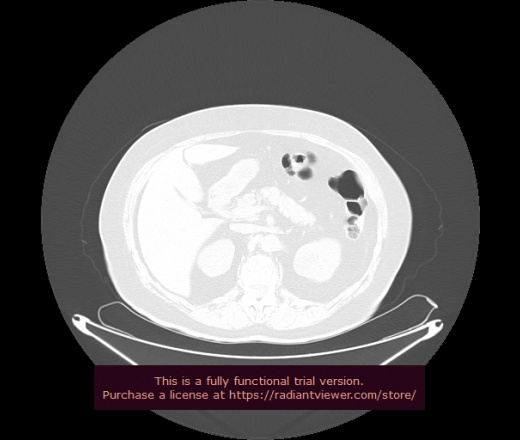

Уважаемые коллеги, если имеется интерес, сможете ли Вы спрогнозировать дальнейшее +-одинаковое течение процесса у 4 данных разных пациентов? Зацепиться где-то можно очень просто, где-то нельзя.